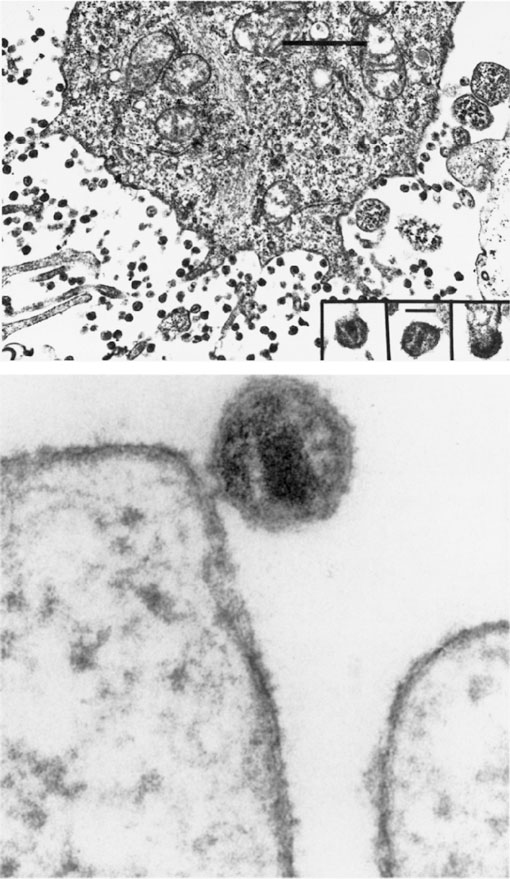

РИСУНОК 16.1. Вирус, вызывающий СПИД. (Сверху) Инфицированный CD4+ Т-лимфоцит, продуцирующий вирус. Мелкие включения представляют собой вирусные частицы, накапливающиеся в культуральных жидкостях. Размер вириона составляет примерно 110 нм. (Снизу) ВИЧ, возникающий на поверхности клетки. Увеличение: ×180 000. Обратите внимание на характерное для ВИЧ образование в вирионе в форме усеченного конуса. Микрофотография любезно предоставлена Робертом Галло.